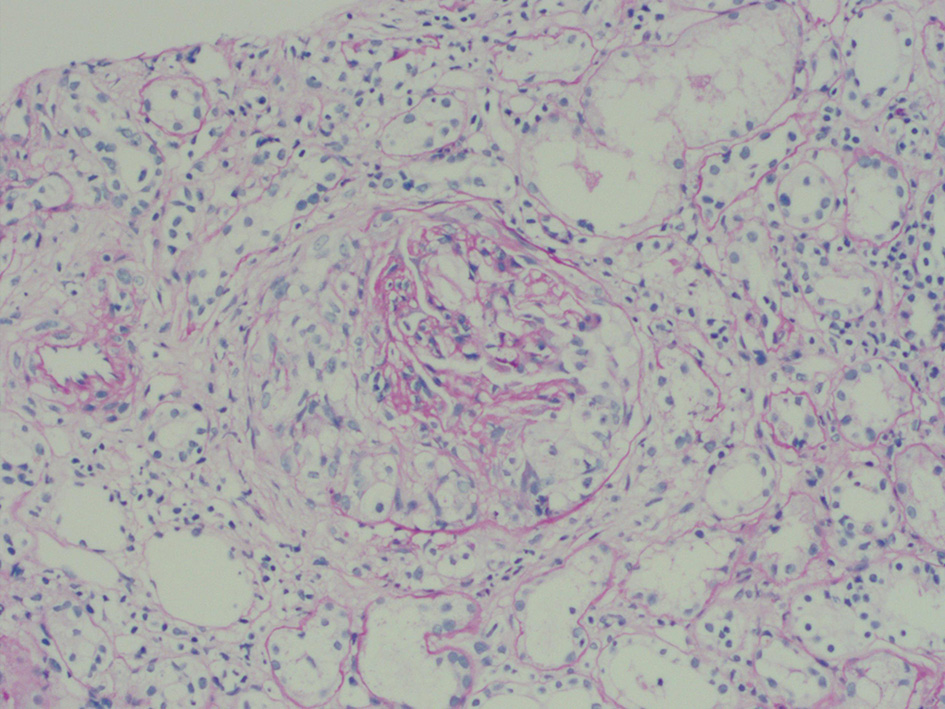

Light microscopy revealed 72 glomeruli, of which 8 were globally sclerosis, 2 were segmental sclerosis, 39 were large cellular crescents, 5 were small cellular crescents, cellular crescents account for 61%, which suggested crescentic glomerulonephritis (Figure 2). In addition, the biopsy revealed moderately increased cellularity with both mesangial and segmental endocapillary proliferation. The tubulointerstitial region demonstrated swelling of the tubular epithelial cells, multifocal tubular atrophy (~50%) accompanied by interstitial fibrosis (~15%), moderate interstitial inflammation, and no evidence of extraglomerular vasculitis.

Figure 2

Light microscopy revealed 44 cellular crescents in 72 glomeruli.